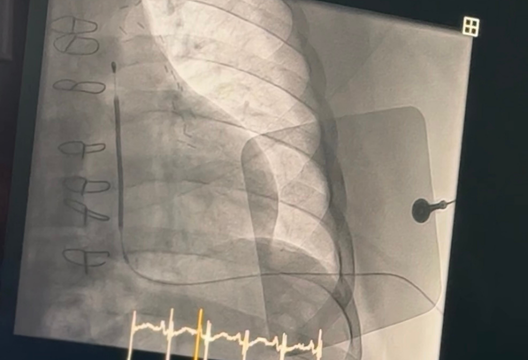

Also, as part of the master class, an expert from Italy presented the technology of implantation of the subcutaneous EMBLEM™ S-ICD System, which provides a safer alternative. This device does not require the insertion of an electrode into the heart, but is placed under the skin above the sternum. The pulse generator itself is placed on the left side of the chest, next to the ribs. Thus, the EMBLEM system does not affect the heart and blood vessels. This makes the device suitable for patients of different ages, reducing the risk of serious complications and, if necessary, making extraction easier and faster.

“It is important to note that during the implantation of the new system, the Serratus regional anesthesia technique was used to reduce discomfort for the patient during the procedure, as well as to eliminate the use of general anesthesia, thereby speeding up the recovery of patients after the procedure,” added Omirbek Nuralinov, Head of Interventional Arrhythmology at the UMC Heart Center.